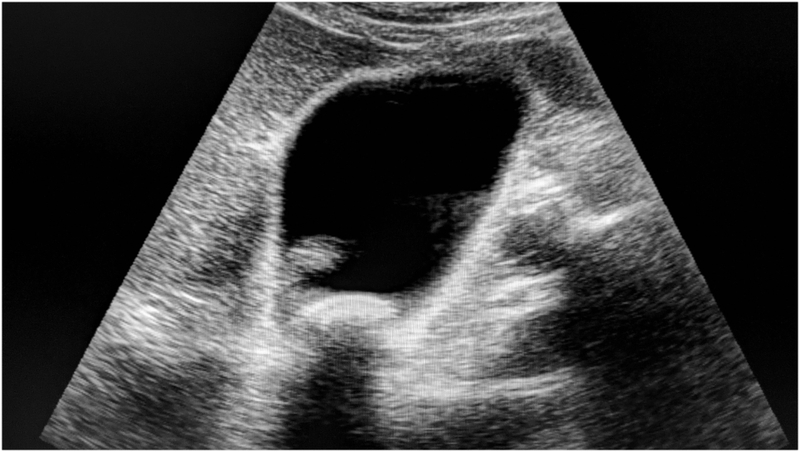

• Siêu âm: Là phương pháp đầu tay trong chẩn đoán sỏi mật, giúp bác sĩ quan sát hình ảnh của túi mật và phát hiện sỏi.

Siêu âm là phương pháp áp dụng phổ biến để chẩn đoán sỏi mật